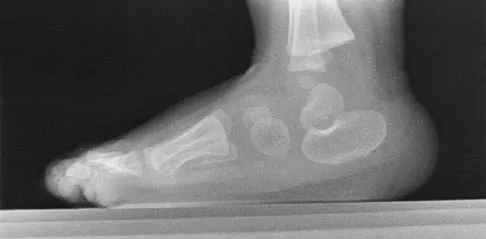

Where is the watershed zone for tarsal navicular vascularity?

The central one third has been established as the watershed zone by angiographic studies, and has been borne out in clinical conditions involving the navicular, such as stress fractures and osteonecrosis. These findings account for the susceptibility to injury at this level. Nunley JA, Pfeffer GB, Sanders RW, et al (eds): Advanced Reconstruction: Foot and Ankle. Rosemont, IL, American Academy of Orthopaedic Surgeons, 2004, pp 239-242.